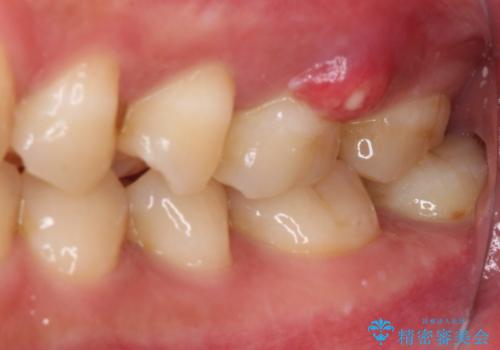

初診時の診察所見では、破折の可能性は低く、根管治療を前提とした治療にて説明をしておりました。

詰められた材料や壊死した組織を除去したところ、鮮明な破折線が認められたため、速やかに抜歯し、傷や骨の治癒を待って、サイナスリフトにより骨高さの低い部分にインプラント埋入を行いました。